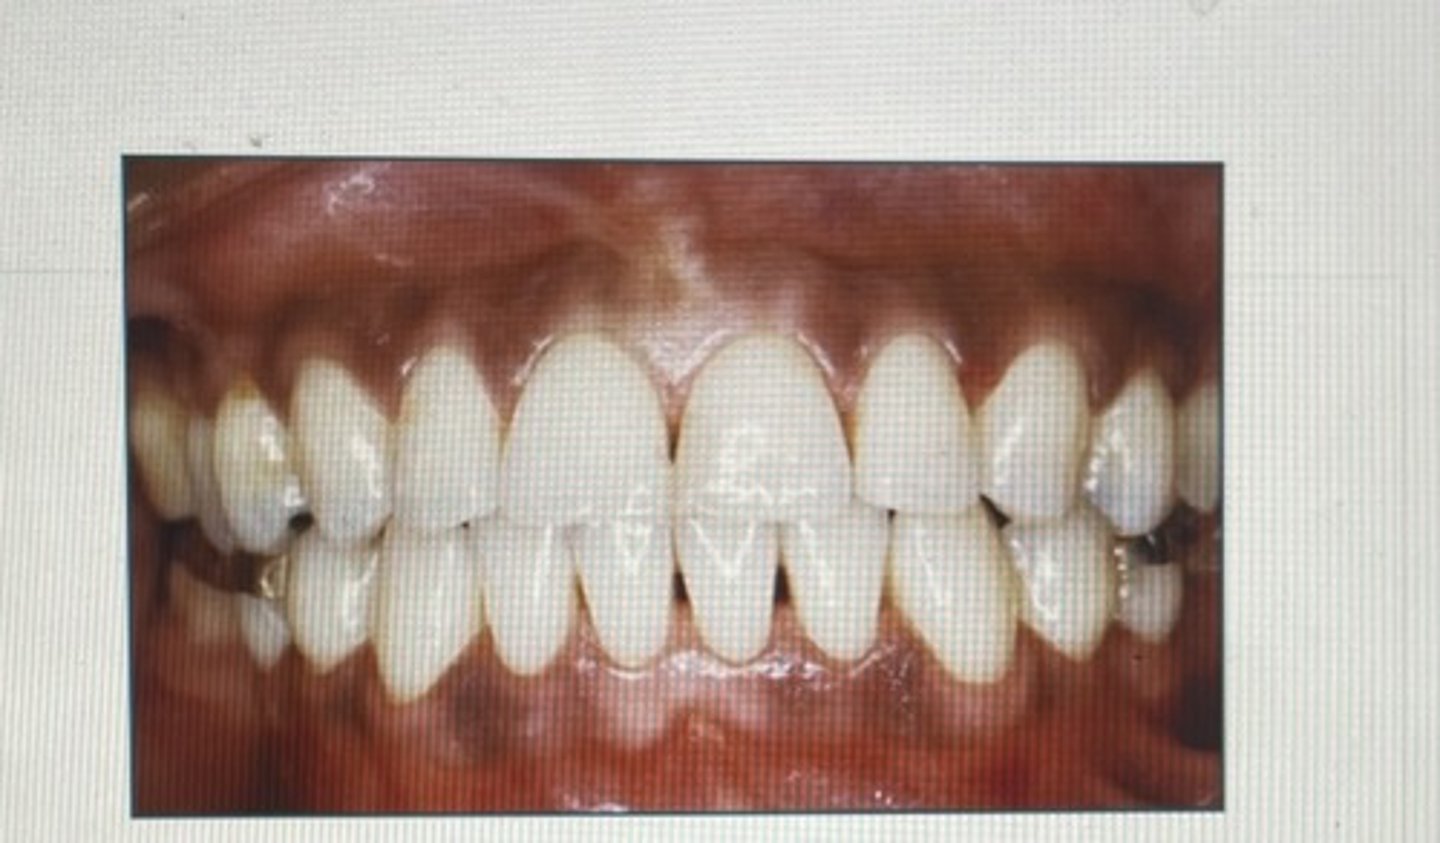

class I occlusion

considered neutral. the mesiobuccal cusp of the maxillary first molar aligns with the buccal groove of the mandibular first molar